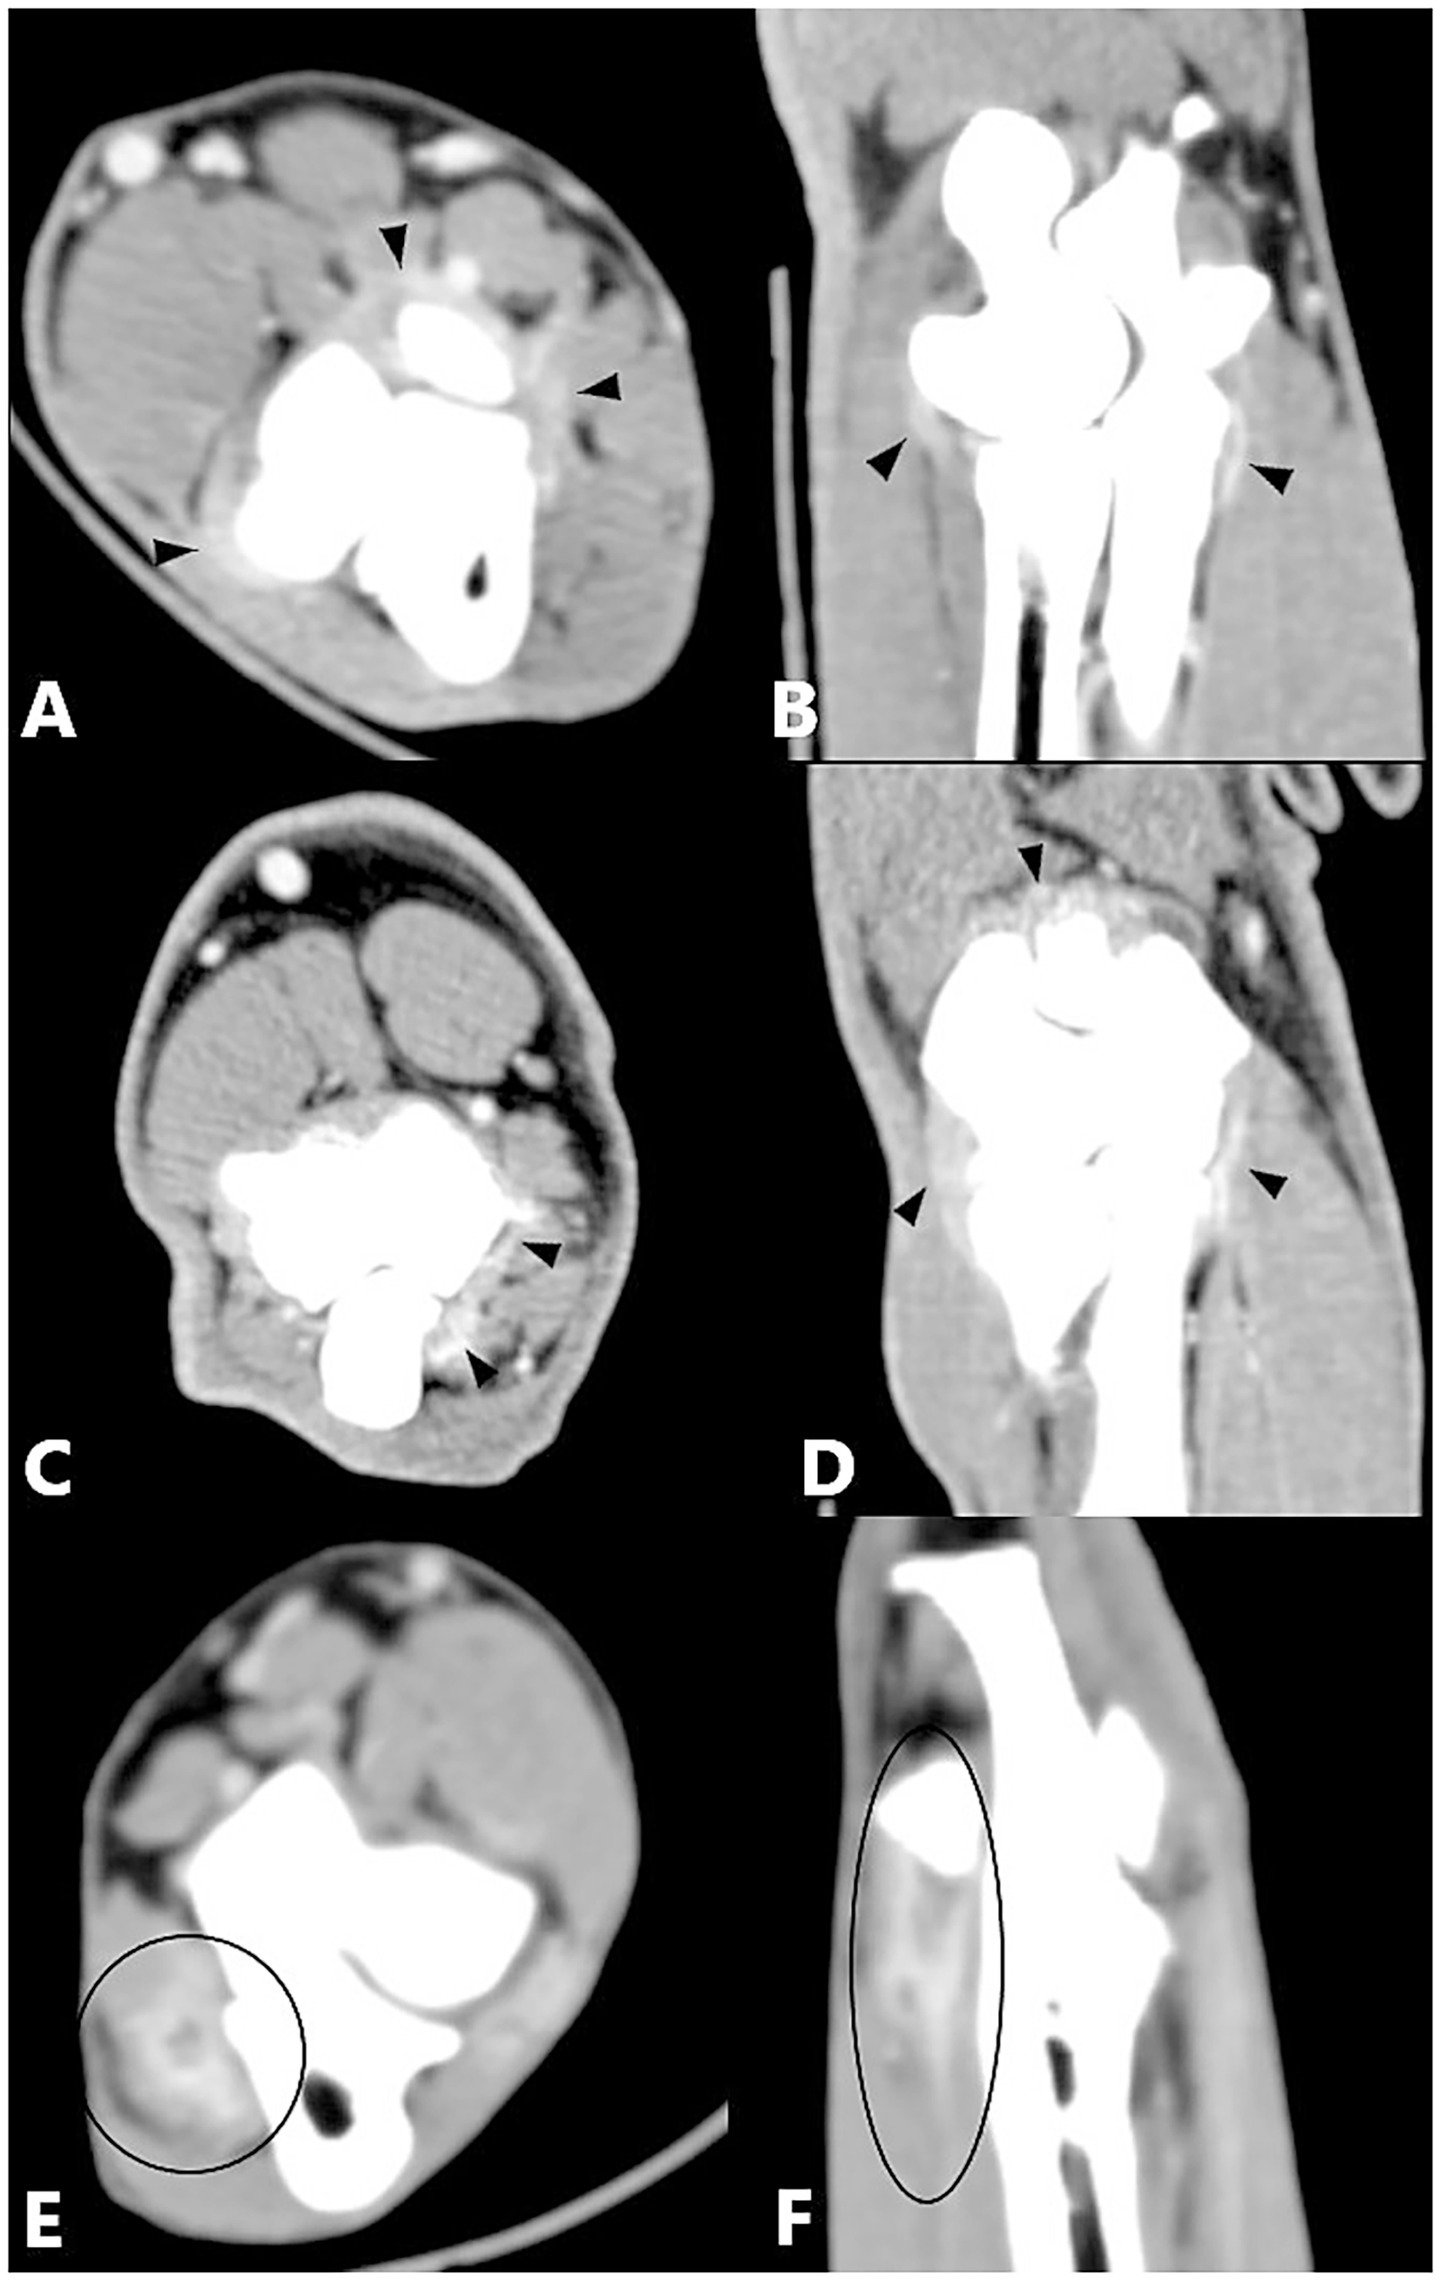

The primary diseases described below generally included additional periarticular osteophytes, which is not listed separately. Periarticular osteophytes were analyzed separately. There was a significant correlation between MCPD (n = 196), UAP (n = 3), and enhancement of the joint capsule compared with the control group. An epicondylar spur (n = 8) showed a significant correlation with flexor muscle enhancement compared with the control group (Figure 3). No significant difference from the control group was observed for other single primary diseases and no statistical significance could be calculated where enhancement was absent or case numbers were insufficient (Table 7).

Figure 3

Figure 3. Computed tomography slices of elbow joints with a single primary disease showing significant correlation with contrast enhancement of the joint capsule or flexor muscles. (A,B) Left elbow joint with MCPD showing contrast enhancement of the joint capsule (black arrowheads). (C,D) Right elbow joint with UAP showing contrast enhancement of the joint capsule (black arrowheads). (E,F) Left elbow joint with an epicondylar spur showing contrast enhancement of the flexor muscles (black circle).